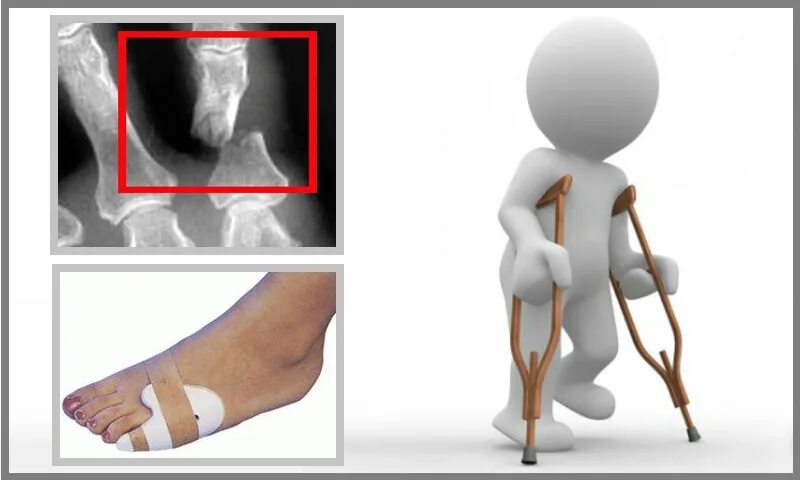

Сколько срастается перелом мизинца